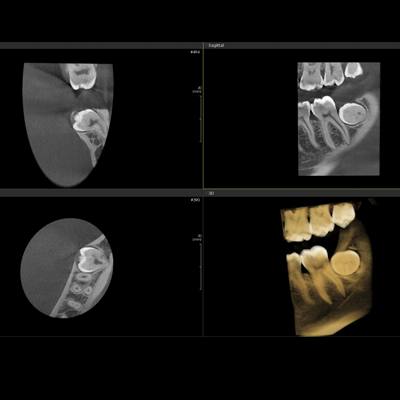

PAPAYA 3D

Diaqnostik kompyuterli erqonomik rentgen sistemi

-3D CT, Panorama

-Çoxsaylı -FOV seçimi (4×5, 14×14)

-Açıq yerləşdirmə (üzbə - üz)

-Çoxsaylı Fokuslanma

-70um görüntülü ENDO rejim